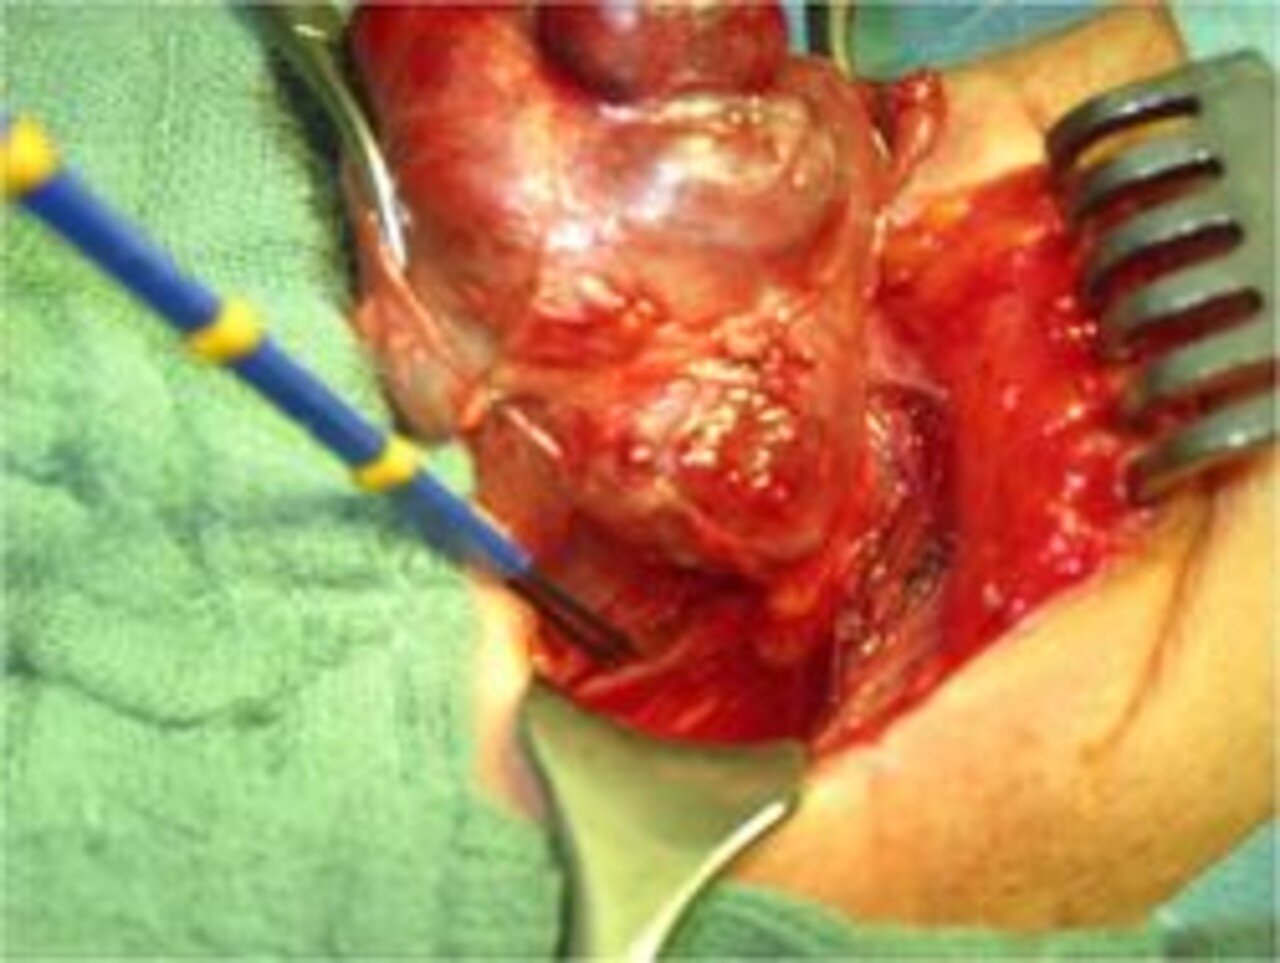

Die große Erfahrung auf dem Gebiet der Schilddrüsenchirurgie befähigt die Chirurgen am Ev. Diakoniekrankenhaus Freiburg auch in Entwicklungsländern anspruchsvolle und schwierige Schilddrüsenoperationen unter einfachen Bedingungen durchzuführen. Unter der Schirmherrschaft von „Operieren in Afrika e. V." www.operiereninafrika.de operieren wir seit 19 Jahren regelmäßig in Burkina Faso Patienten mit ausgeprägten Schilddrüsenerkrankungen.